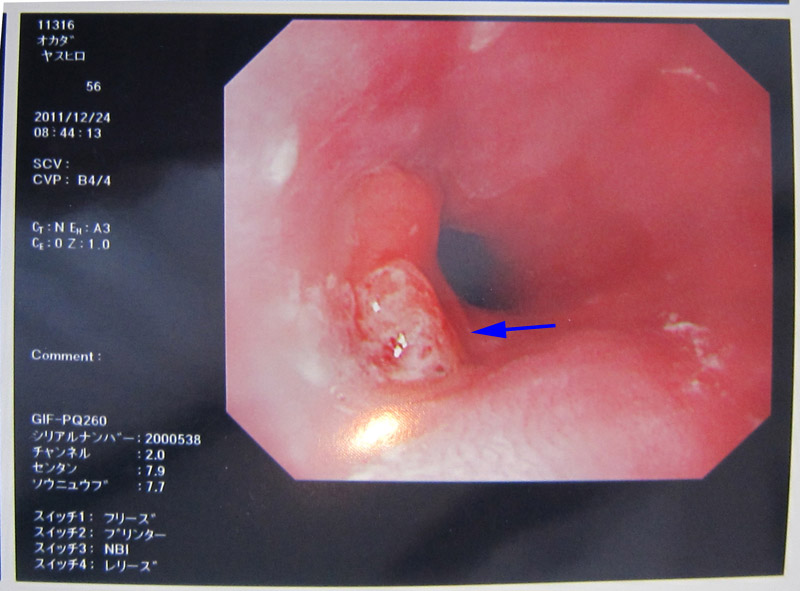

2.がん(食道がん手術2012年5月11) |

| 内視鏡検査(胃カメラ) |

切り取った癌細胞 |